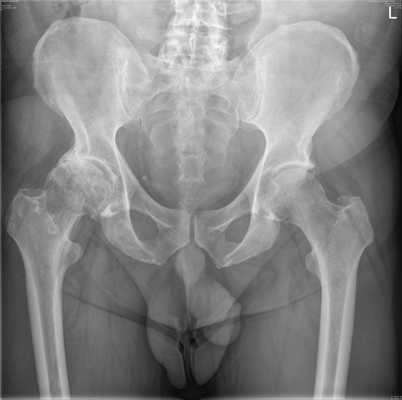

Рентген костей таза

Таз представляет собой часть скелета, которая расположена в основании позвоночного столба. Он не только является опорой для внутренних органов, но и обеспечивает фиксацию к туловищу ног. Именно поэтому его здоровье играет немаловажную роль, а рентген костей таза является неотъемлемой составляющей диагностики при заболеваниях и травмах этой области.

Он является диагностическим высокоинформативным методом, позволяющим получить данные о состоянии костных структур и суставов таза, определить повреждения и патологии мягких тканей и внутренних органов. Рентгенографию широко применяют в поликлиниках, поэтому она является доступным методом, в том числе и в ценовом плане. Пройти рентген костей малого и большого таза можно в диагностическом центре многопрофильной клиники ЦЭЛТ. Мы располагаем современным оборудованием, а наши специалисты практикуют индивидуальный подход, что неизменно позволяет добиваться высокого качества рентгенографических снимков.